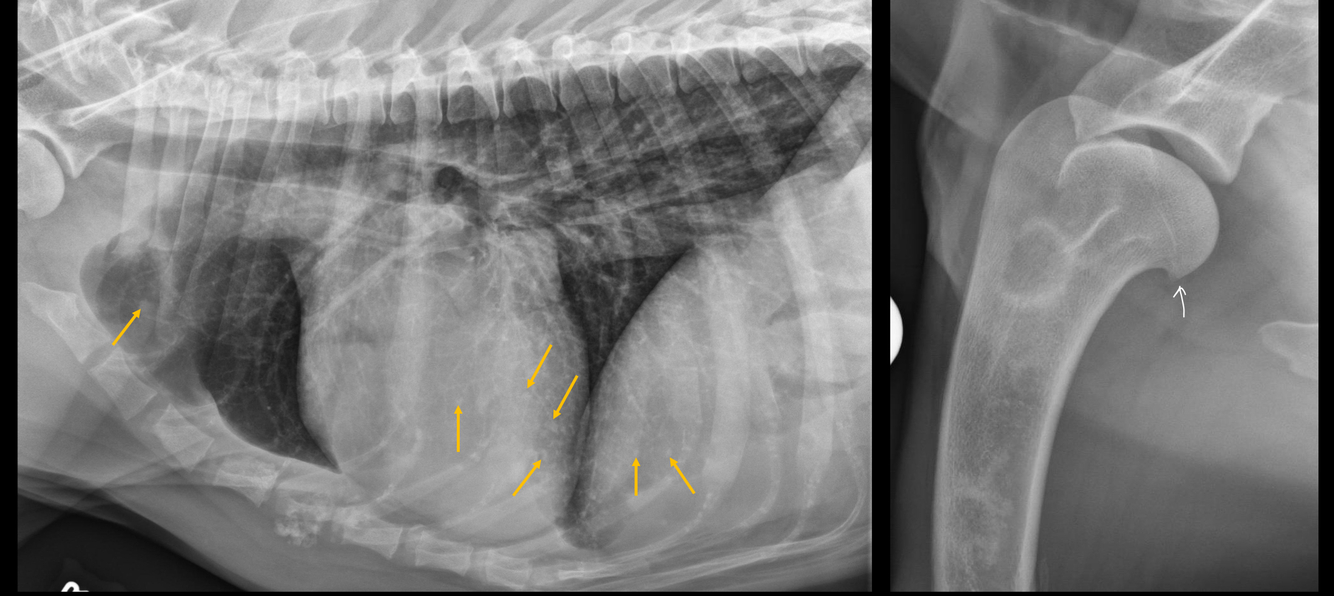

Q

What is seen on this radiograph?

A

• malpositioned stomach with gas within gastric wall (pneumatosis gastri)

• also gas within portal vasculature

GDV!